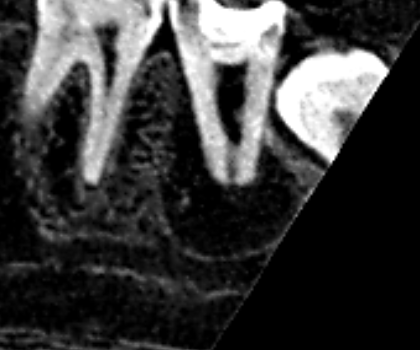

下顎第二大臼歯の初診時の水平断のCT画像です。歯根は雨樋状をしており、根管は黒い2根管しか清掃されていません。樋状根は、根管清掃も雨樋状の清掃が必要です。